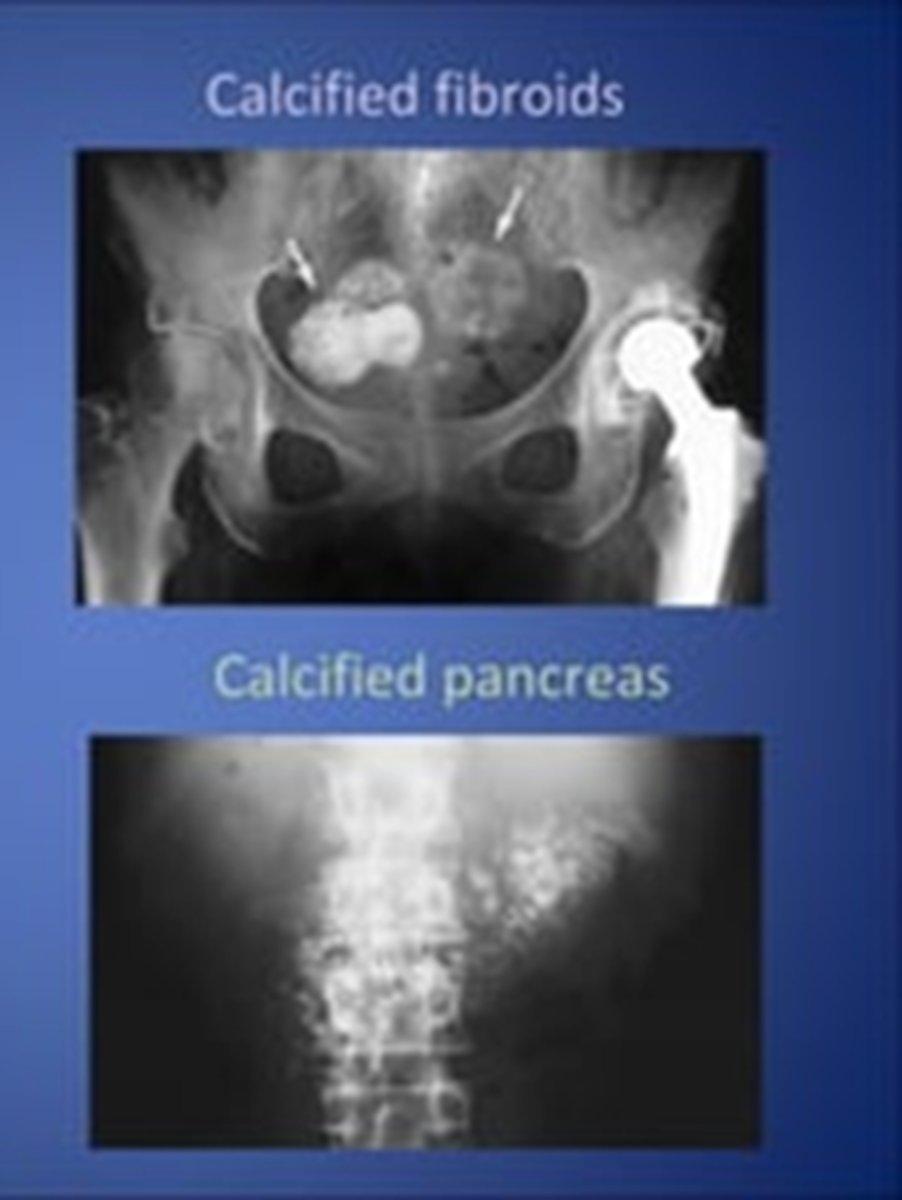

etiology of most calcifications can be determined by evaluatin

anatomic location, pattern of calcification